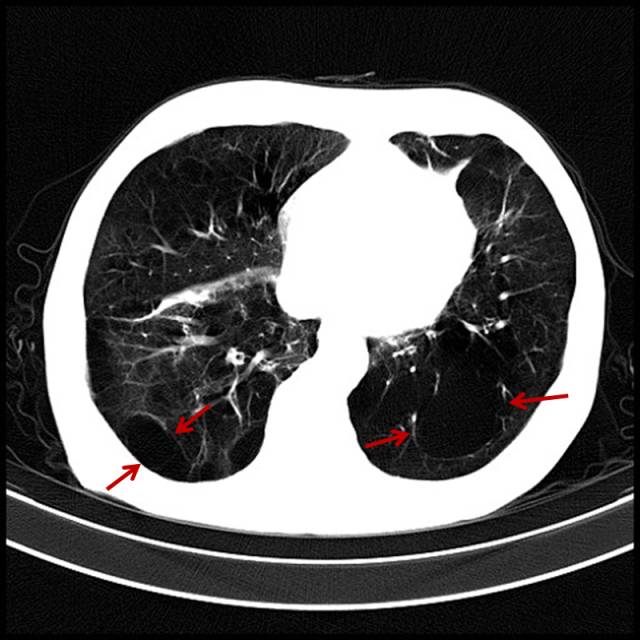

■吸烟导致双肺坠积效应

男,47岁,吸烟者,每天2盒。

2.吸烟导致的肺坠积效应

男,35岁,吸烟,最明显感觉是游泳憋气困难。